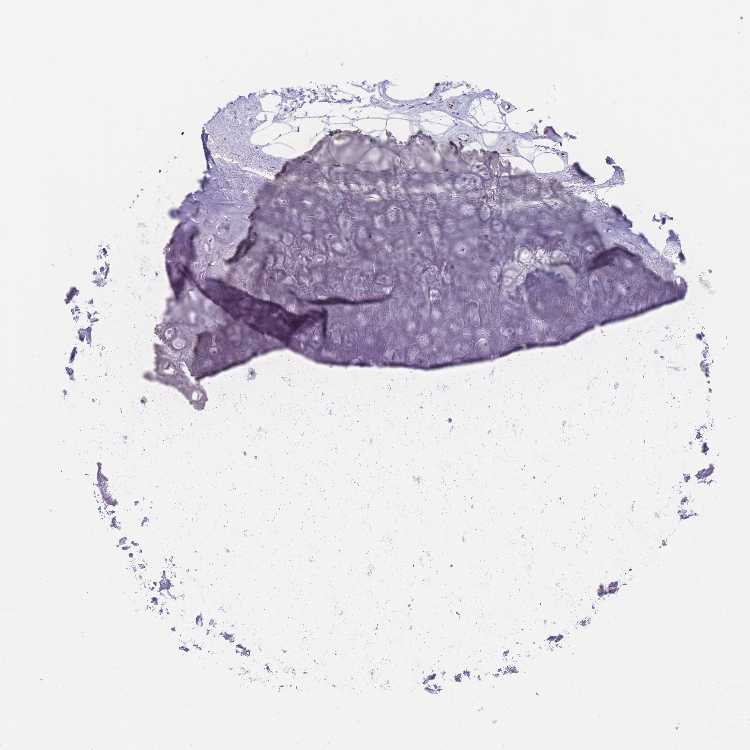

SOFT TISSUE 1 - Antibody stainingi

Antibody staining in the annotated cell types in the current human tissue is reported as not detected, low, medium, or high, based on conventional immunohistochemistry profiling in selected tissues. This score is based on the combination of the staining intensity and fraction of stained cells.

Each image is clickable and will lead to virtual microscopy that enables deeper exploration of all samples and also displays staining intensity scores, fraction scores and subcellular localization as well as patient and tissue information for each sample.

Antibody HPA049518

Chondrocytes Not detected

Fibroblasts Not detected

Peripheral nerve Not detected